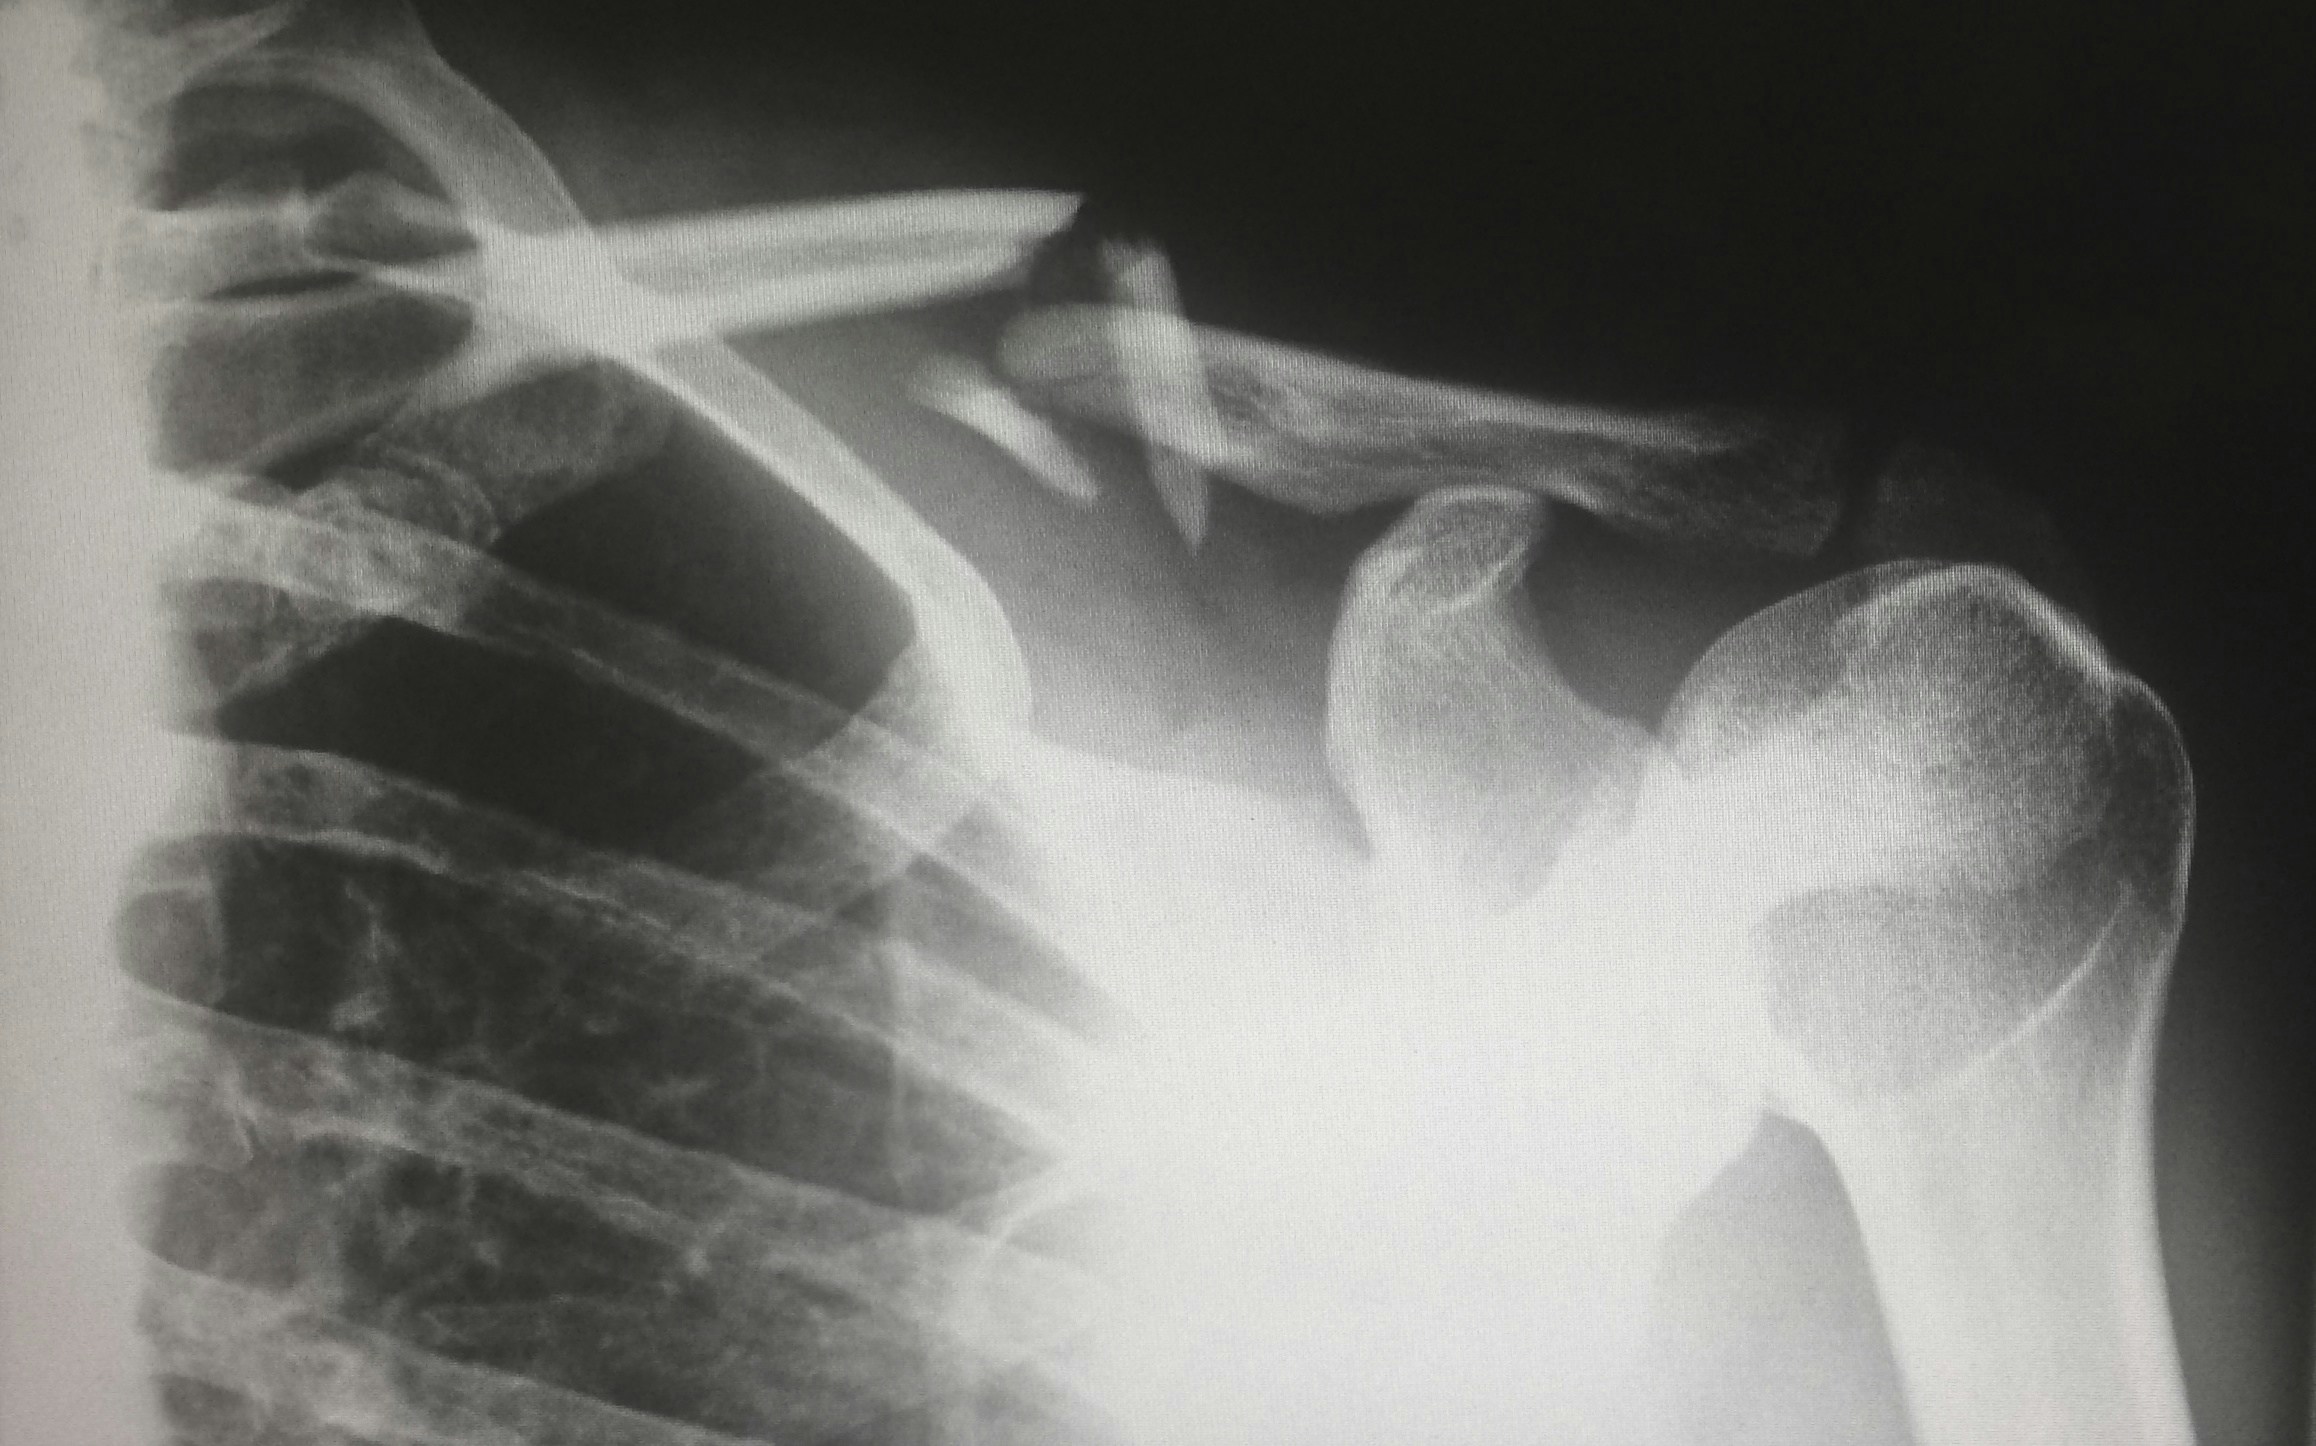

People consumed, on average, about 8 servings of ultra-processed foods per day, according to the study, which involved more than 160,000 participants from the UK Biobank database. For every 3.7 extra servings eaten per day, the risk of hip fracture increased by 10.5%.

The study analysed data from 163,855 participants from the UK Biobank for over 12 years. It found that high intakes of ultra-processed foods were linked to a reduction in bone mineral density in several areas, including the upper femur and the lumbar spine region. These data were cross matched with records of fractures in hospital records, showing a link between UPF consumption and risk of bone fractures.